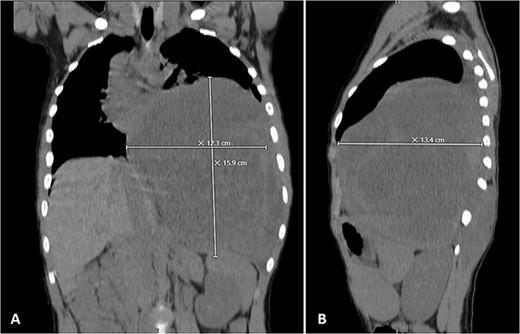

His postoperative course was uneventful. A chest CT was performed following the surgery, and the results revealed that the previous left lung mass had been completely removed without definite residue (Fig. 4). The patient is on close follow-up monthly with a physical exam, chest X-ray, and chest CT every 3–6 months. For the past two years, there have been no discernible clinical or radiological indicators of recurrence (Fig. 5).

Selected axial cuts of the patient’s chest–lung window. The previously mentioned left posterior chest wall mass is no longer seen with post-operative changes noted.